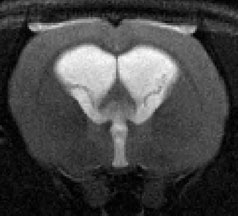

Congenital hydrocephalus is a condition usually marked by an excessive accumulation of cerebrospinal fluid (CSF) within the cerebral ventricles resulting in ventricular enlargement. This condition affects between 0.48 to 0.81 infants per 1000 live births and up to 78% of patients suffer persistent deficits after treatment, possibly due to reactive astrogliosis and microgliosis. Examining this gliosis was the focus of much of my research thus far. My research is currently focusing on genetic links to hydrocephalus. Please read below for more information on my different research projects.

Gliosis in hydrocephalus

Previous studies have shown that there is an increase in glial cells (specifically astrocytes and microglia) due to hydrocephalus. I was able to show that shunting, or insertion of a draining device, effectively reduces the presence of glial cells.